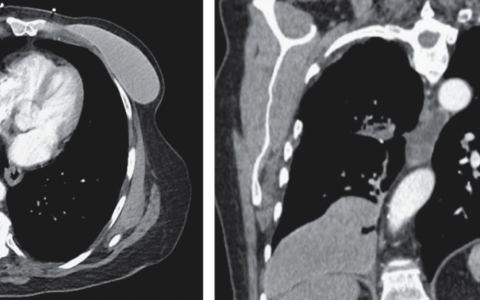

A 29-year-old woman with a history of systemic lupus erythematosus presented to the dermatology clinic with a 2-week history of an itchy, painful rash on her nose and hands. The rash had first appeared 1 day after the weather had turned cold. The patient reported no sun exposure. The physical examination was notable for erythematosus macules and papules with punched-out ulcers on the nose. Scattered papules were seen on the palms, and edematous erythrocyanosis of the fingertips with ulcerations on the lateral aspects was noted. Blood tests were positive for antinuclear antibodies, anti–double-stranded DNA antibodies, rheumatoid factor, anti-Ro antibodies, and antiphospholipid antibodies, and hypergammaglobulinemia was present. Cryoglobulin and cold agglutinin testing was negative. Histopathological examination of a biopsy specimen of the right nasal sidewall revealed vacuolar interface dermatitis and perivascular lymphocytic infiltrate. Which of the following is an important intervention to prevent this finding?

答案是避免寒冷。诊断为寒冷性红斑狼疮,这是一种不常见的皮肤红斑狼疮形式。炎症性皮肤病变是由寒冷暴露引起的,通常发生在手和脚上;鼻子的受累是不常见的。受影响的患者应该被建议穿足够保暖的衣服作为管理和预防措施。